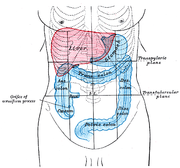

| 22. 11. 2011, 11:16 | Jatra a tluste strevo.png (soubor) |  | 55 kB | Webmaster | 2 | |